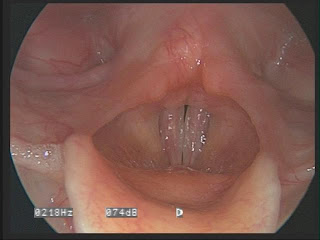

This last video, taken six weeks after surgery shows a completely different set of vocal cords. They come together like normal vocal cords, produce clear sound, and are not incredibly swollen, but rather flexible. Yes, it still sounds breathy (notice the hissing quality to it), but this is because I am still learning the technique that my vocal cords are only now small enough to handle.